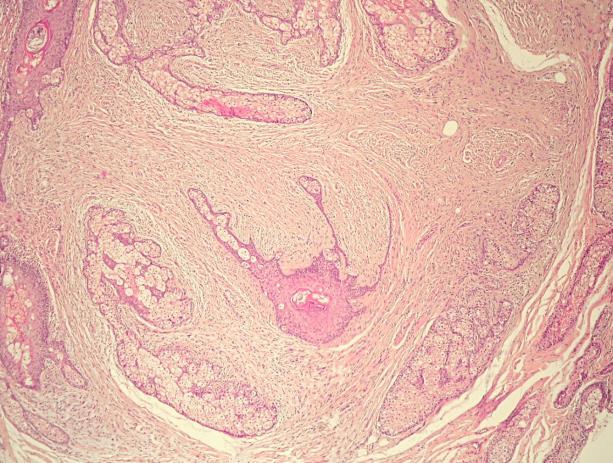

• Spiradenoma

• Multinodular benign eccrine gland derived

• Face/upper trunk

• Admixed basaloid and clear cells

• Brooke-Spiegler syndrome - CYLD

• Cylindroma

• Head and neck

• Well defined nests of basaloid cells in a jigsaw pattern with eosinophilic PAS positive basement membrane-type material

• Brooke-Spiegler syndromeCYLD